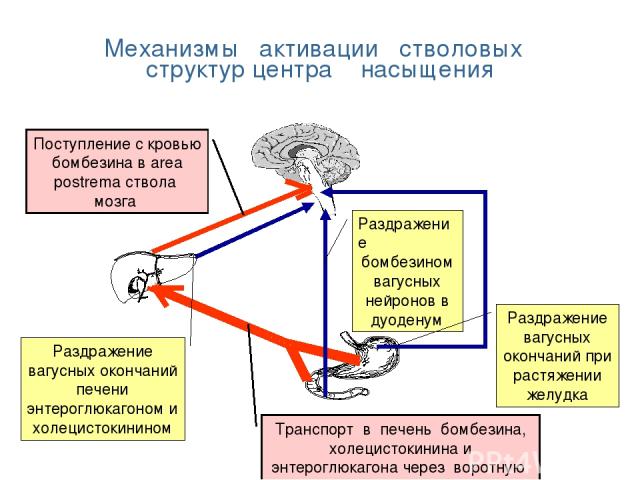

Как работает центр насыщения в гипоталамусе: визуальные иллюстрации

Раздел: Образы вокруг